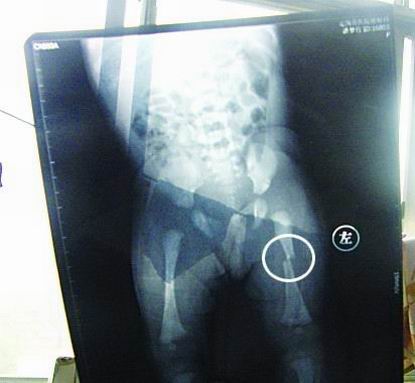

CT顯示小夢竹左下肢骨折

今年7月2日下午,定陶縣南王店鄉沈莊村孕婦聶元真,在定陶縣人民醫院剖腹產下一女嬰,取名為潘夢竹。醫院說,嬰兒出生后窒息,診斷為新生兒缺血缺氧性腦病,頭皮血腫。當晚發現女嬰左下肢部位異常,第二天拍片顯示為左下肢骨干骨折。7月3日,潘夢竹的頭顱CT顯示其頭頂部骨折,蛛網膜下腔出血,顱內血腫。